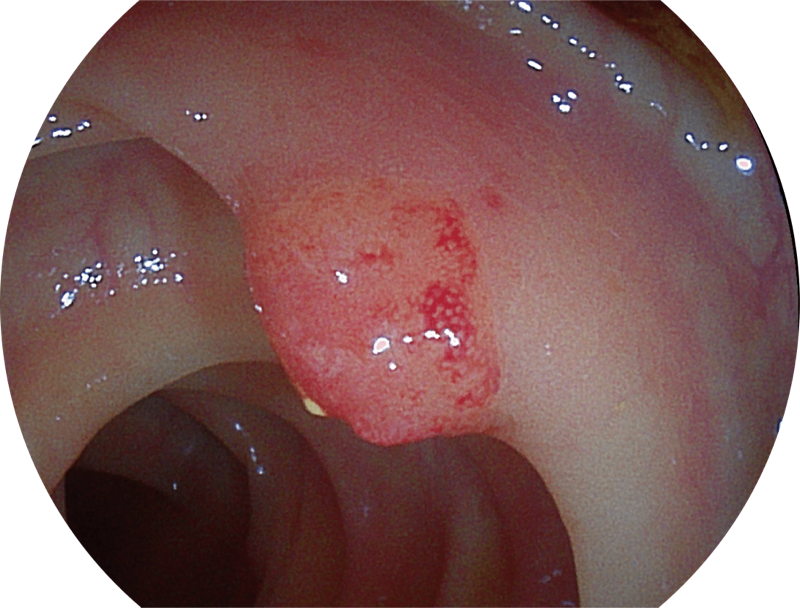

(Versatile Intelligent Staining Technology)

能够凸显黏膜浅层血管轮廓和黏膜表面微结构,适用于中、近景观察下的早癌精确诊断。

能够凸显黏膜浅层和中层血管轮廓,适用于中、远景观察下的病灶识别和早癌筛查。